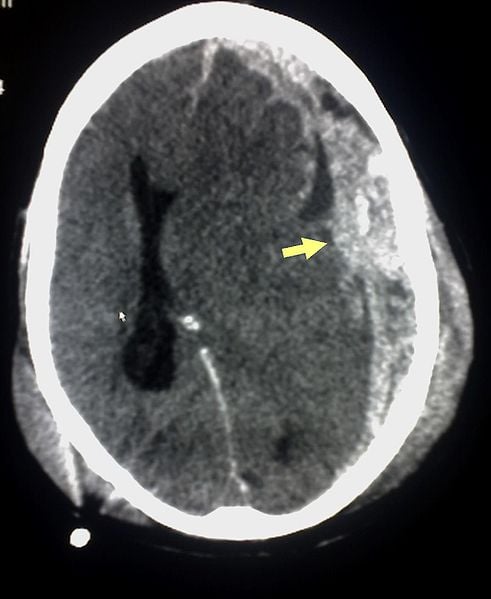

Image Source: The CT scan of a subdural hemorrhage resulting from TBI is available in the public domain.